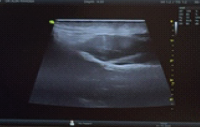

Computed tomography (CT) and magnetic resonance imaging confirmed an AO Type B2, N0, M3 fracture at C7 in a fused ankylosed spine (Fig. 1). Global sagittal profile assessment showed severe thoracic kyphosis with chin-brow vertical angle (CBVA) of 62° and sagittal vertical axis (SVA) of +8 cm. The kyphotic apex was localized at D5 on radiographs and CT.

Figure 1: (a) Preoperative clinical photograph showing rigid thoracic kyphosis with impaired horizontal gaze. (b) Preoperative computed tomography scan sagittal reconstruction demonstrating fused ankylosed spine and AO type B2 fracture at C7.